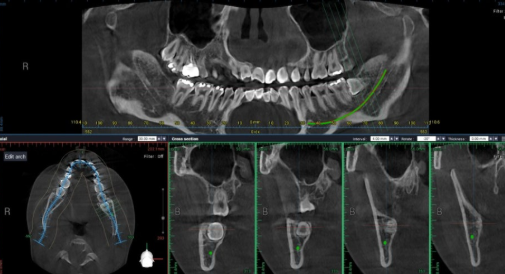

임플란트나 사랑니 수술 전에 촬영하는 덴탈 CT의 경우는 30μSv로 조금 더 높은 수치지만,

국가건강검진에서 시행하는 흉부 엑스레이의 약 1/3 수준에 불과합니다.

예를 들어, 임플란트를 하려면 턱뼈의 높이, 폭, 신경과의 거리까지 정확히 알아야 하는데,

이를 확인하지 않고 진행하면 부작용 확률이 높아집니다. 이런 상황에서는 오히려 촬영을 안 하는 것이 더 큰 위험을 초래할 수 있습니다.

실제로 저희 병원에서도 엑스레이 촬영 시 의료진은 항상 환자의 상태와 촬영 목적을 먼저 고려한 후, 필요 최소한의 촬영만을 시행합니다.